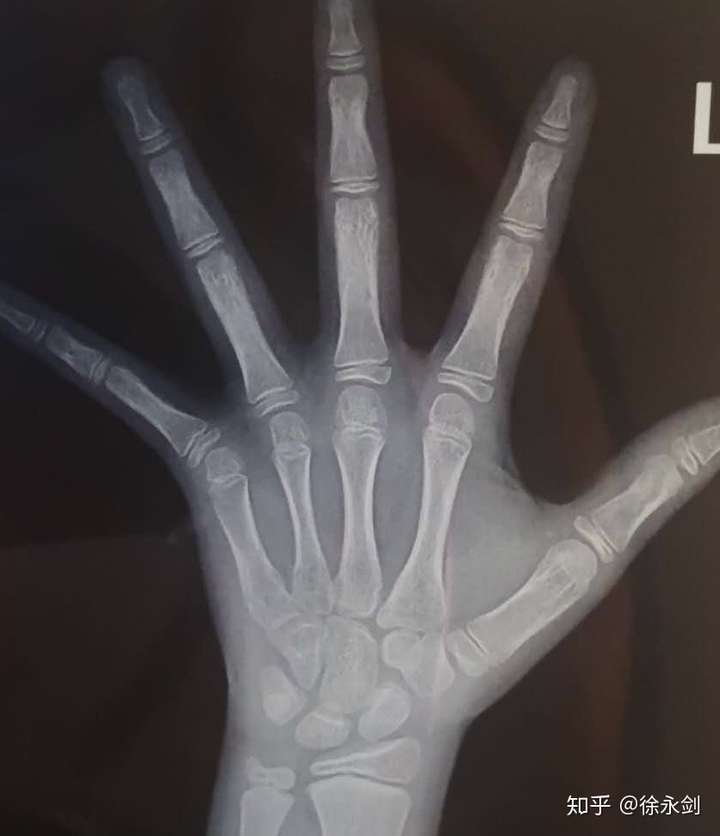

生长发育科徐永剑所长

中华05测骨龄

图片尺寸1080x1439